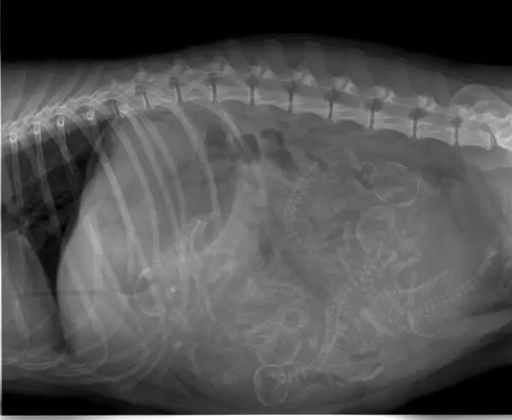

I see 5 of them.

Am I the only one seeing tiny alien kids from the Aliens movie?

Pregnant women should avoid people that got a x-ray recently but dogs can have x-ray during pregnancy?(edit) wrong apparently, I don’t even know where I got this from

People and dogs who have been recently x-rayed are not a danger to others. They don’t suddenly start giving off radiation themselves (above background levels).

I’ve never heard about pregnant women having to avoid people who had a recent x-ray. According to the Mayo Clinic: “The possibility of an X-ray during pregnancy causing harm to a fetus is very small. Generally, the benefits of the information from an X-ray outweigh the risks.”

I think you might be confusing it with midly radioactive injections. My gf was given one to study how well her lyph nodes function and distribute the liquid. She was tol not to hang around pregnant people too long.

Hopefully dogs are more resistant to X-rays than we are : we stopped X-raying pregnant people because the babies had very high leukemia rates afterwards…